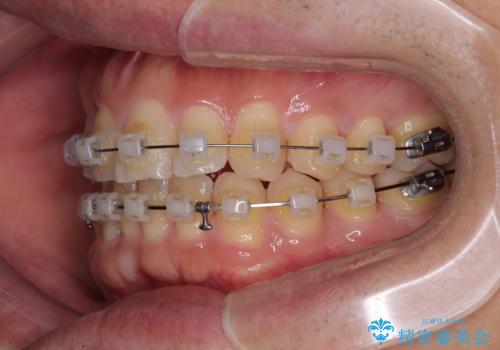

- クリアブラケット

- 1年1ヶ月

- 上下前歯のデコボコを気にして来院された患者様です。

ワイヤー矯正でもマウスピース矯正でも可能でしたが、短期間で、自身の手を煩わせることなく治療を行いたいとのことで、ワイヤー装置にて矯正治療を行うこととしました。

上顎前歯の舌側転位が顕著であったため、治療期間が長くなると思われましたが、僅か1年で無事に終えることができました。